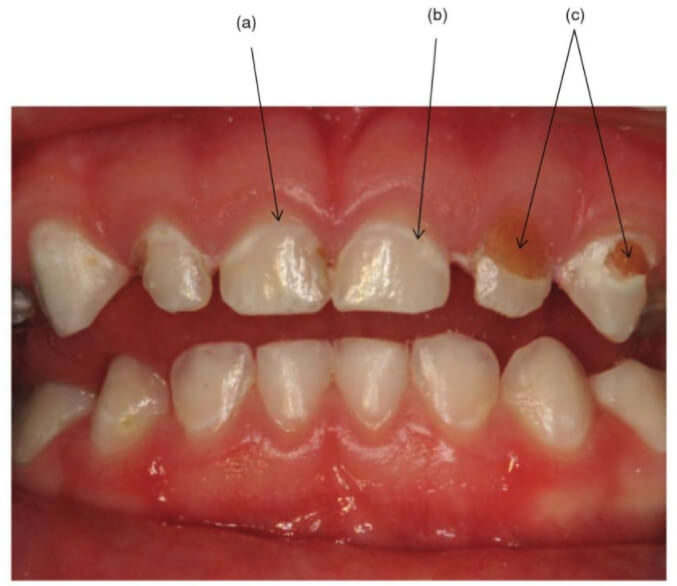

小朋友怎麼這類型的蛀牙稱之為 Early Childhood caries ( ECC ),在高風險族群中其蛀牙進展速度非常的快,所以通常家長發現牙齒上有洞或是因疼痛就診時,大多都已經發展成很深的蛀牙。

另外要特別提的是,若是 3 歲以下的小朋友,其牙齒表面就有刷不掉的脫鈣(通常會在門牙靠近牙齦處有帶狀的白斑),這就是一種蛀牙的警訊,這類小朋友屬於隱性的蛀牙高風險族群。通常會建議積極的做口腔清潔,飲食控制,再視情況增加塗氟頻率,降低日後蛀牙快速擴散的機率。